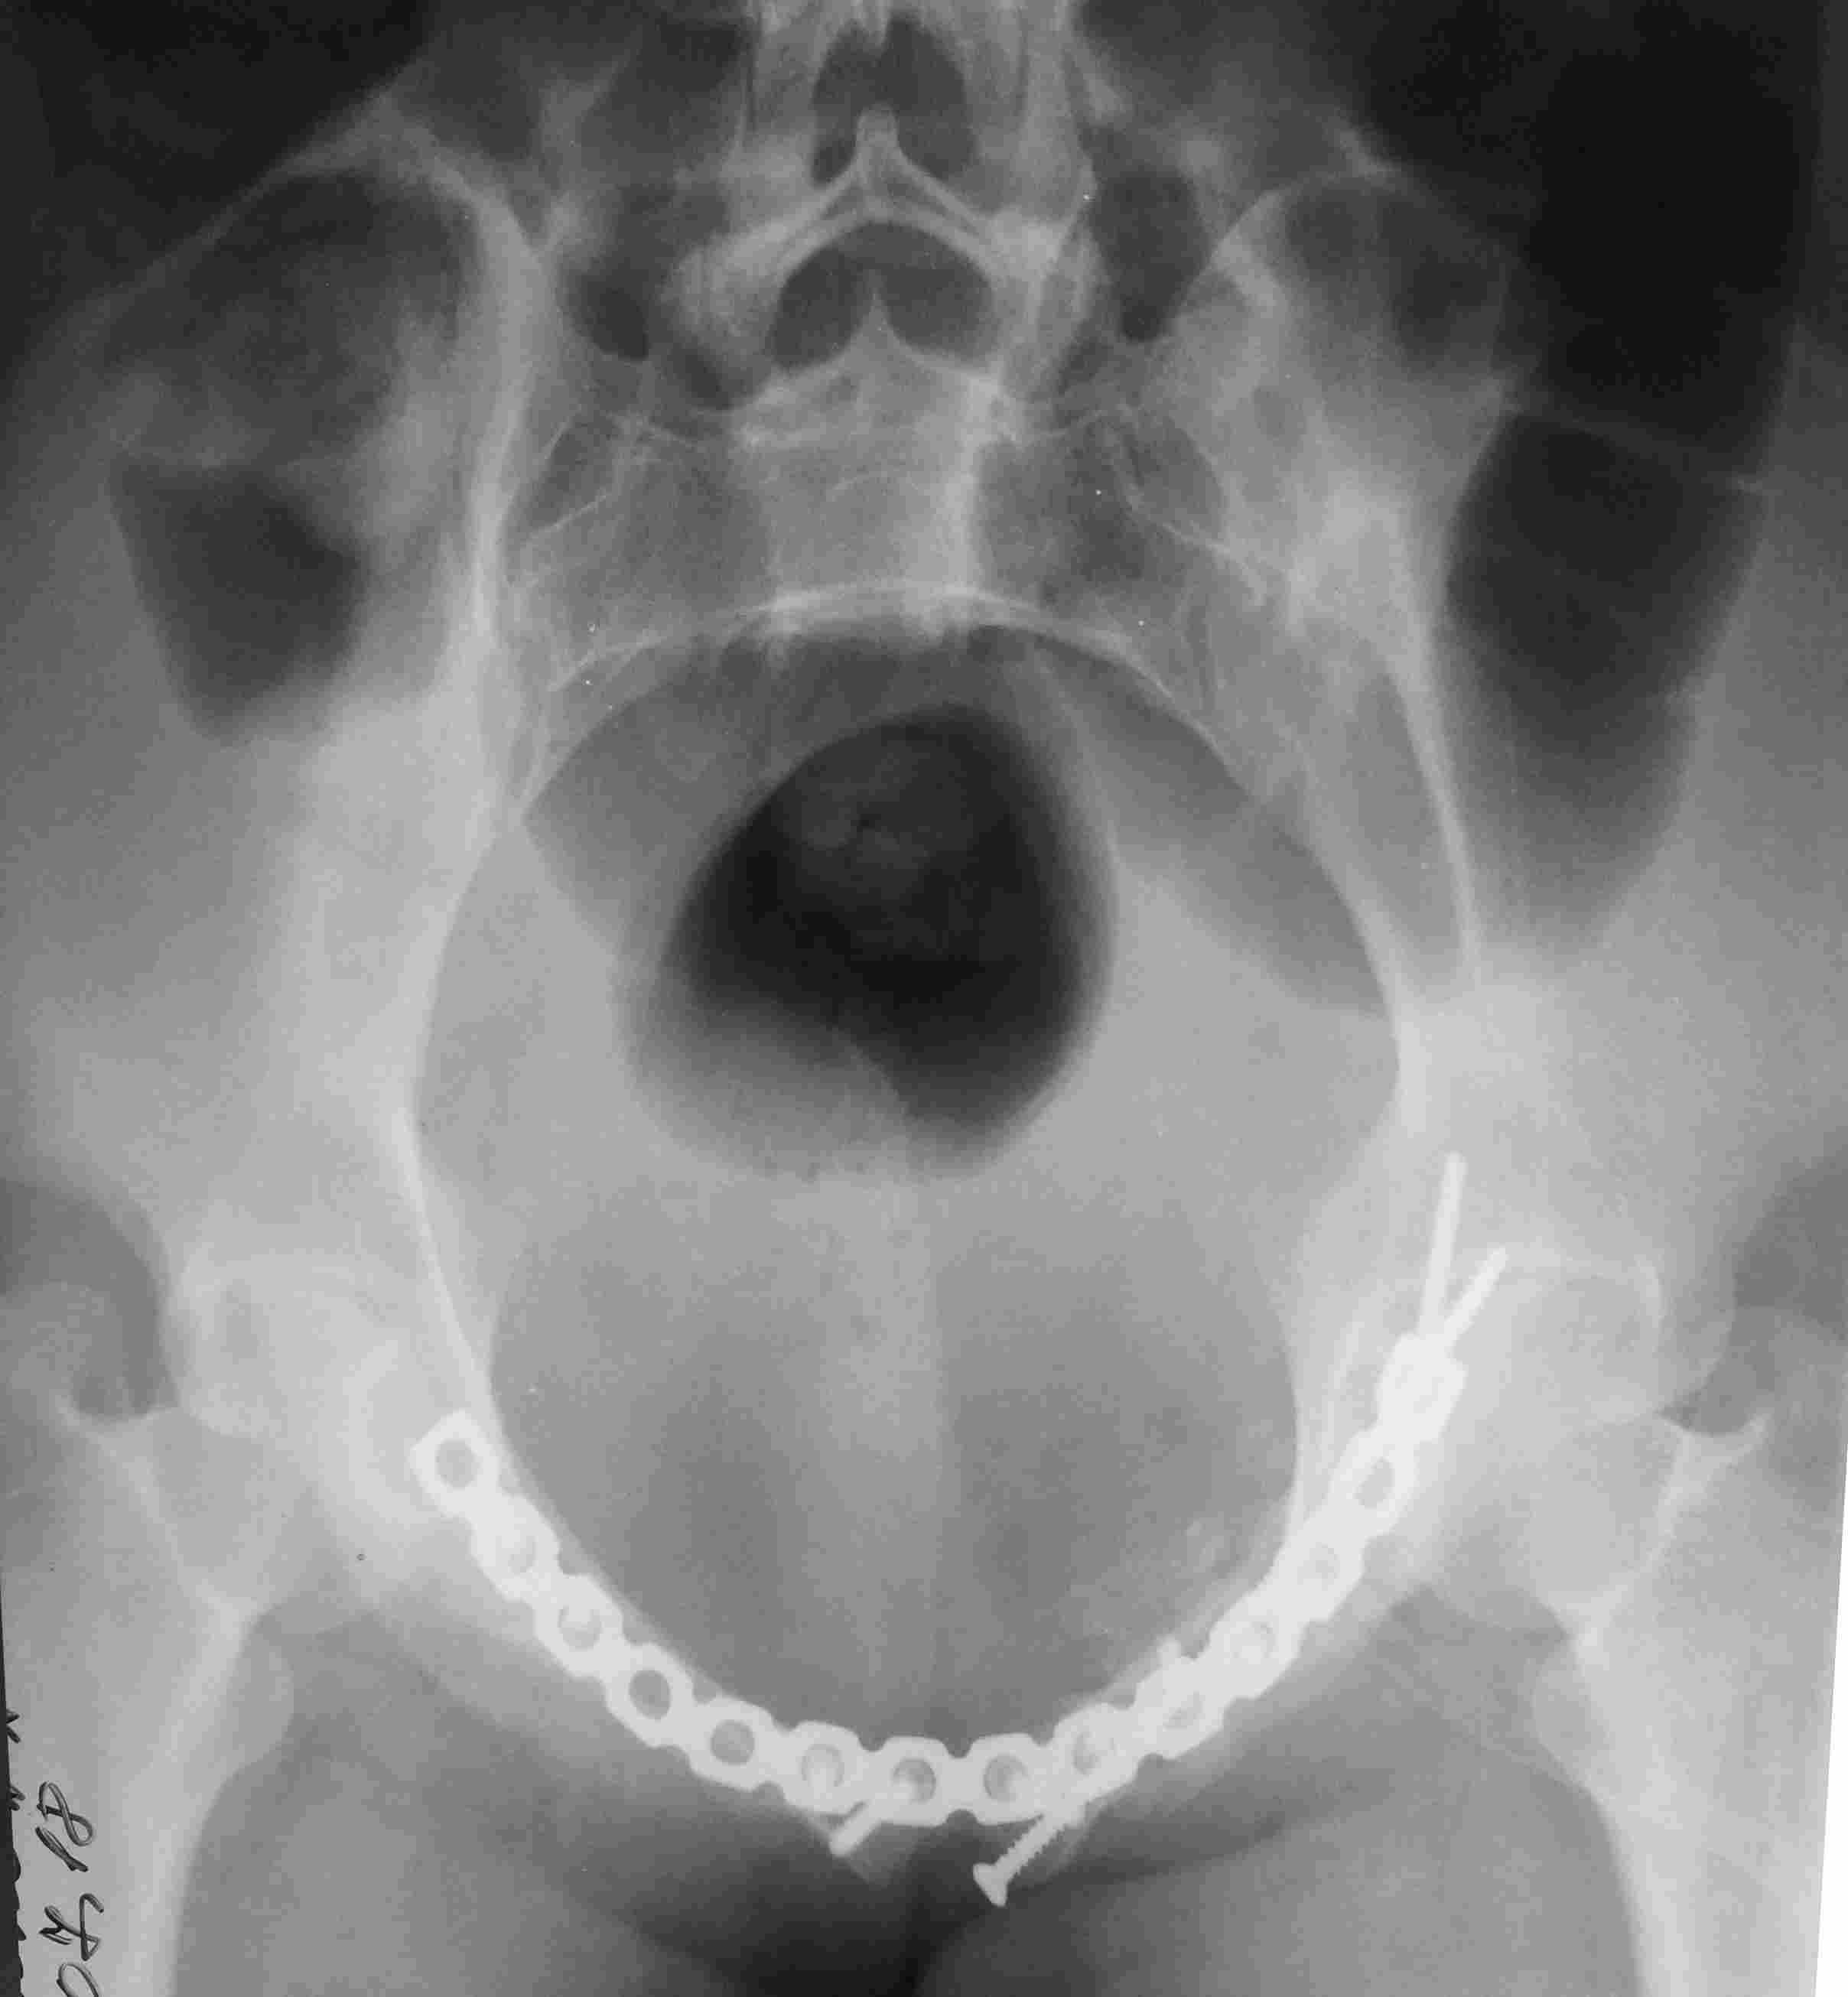

[Ortho] повреждение таза с необычным смещением

Постоп. Верхняя ветвь возле шейки мочевого пузыря, нижняя так же где-то

глубоко в мышцах, ротирована. Обе практически лишены кровоснабжения.

лонное сочленение фактически свободно лежащее, справа  почти целое, но

ветви сломаны возле него. Слева часть лонного сочленения цела на 2/3.

интраоперационно подвижность правой половины таза. Постоп все стабильно,

но все же планирую дополнительно провести IS винт справа.